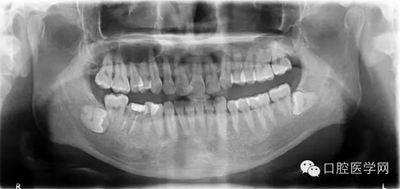

輔查:曲面斷層觀察齒c槽隔情況,為種植支抗植入熟悉解剖。

在本例病例中,我們可以看到常規(guī)腭側植入直徑1.4長8mm的種植支抗,幾乎未鉆入骨皮質內(nèi),當然無法行使功能。 我們往往把治療的失敗歸咎于患者的不配合,實際上自己的操作規(guī)范也要回顧,如此才能發(fā)現(xiàn)問題,增廣經(jīng)驗。 在本病例中,我們最終選取的支抗為12mm長,減去8mm的粘膜厚度,旋入骨皮質不足4mm,初始穩(wěn)定性佳!

①腭大動靜脈及神經(jīng)出腭大孔后在距齦緣5-15mm向前直至切牙孔,植入部位不應超過第二磨牙的遠中,以免傷及腭大孔;

②患者張口有限,會行成植 入角度,容易觸碰牙根。植入位置和角度:牙根之間,冠狀面斜向下,避免過于水平未鉆入牙槽間隔,距離齦緣6mm-8mm之間處,支抗釘與腭部骨面成 70-90°角。

支抗釘選擇:宜選用8×1.4mm支抗釘,并采用彎機頭植入如圖一,以免支抗釘觸碰牙根。患者張口度夠大,也可采用直柄。如圖二提示:因視角不良,腭側種植釘植入建議使用口鏡反復檢查植入角度是否正確。